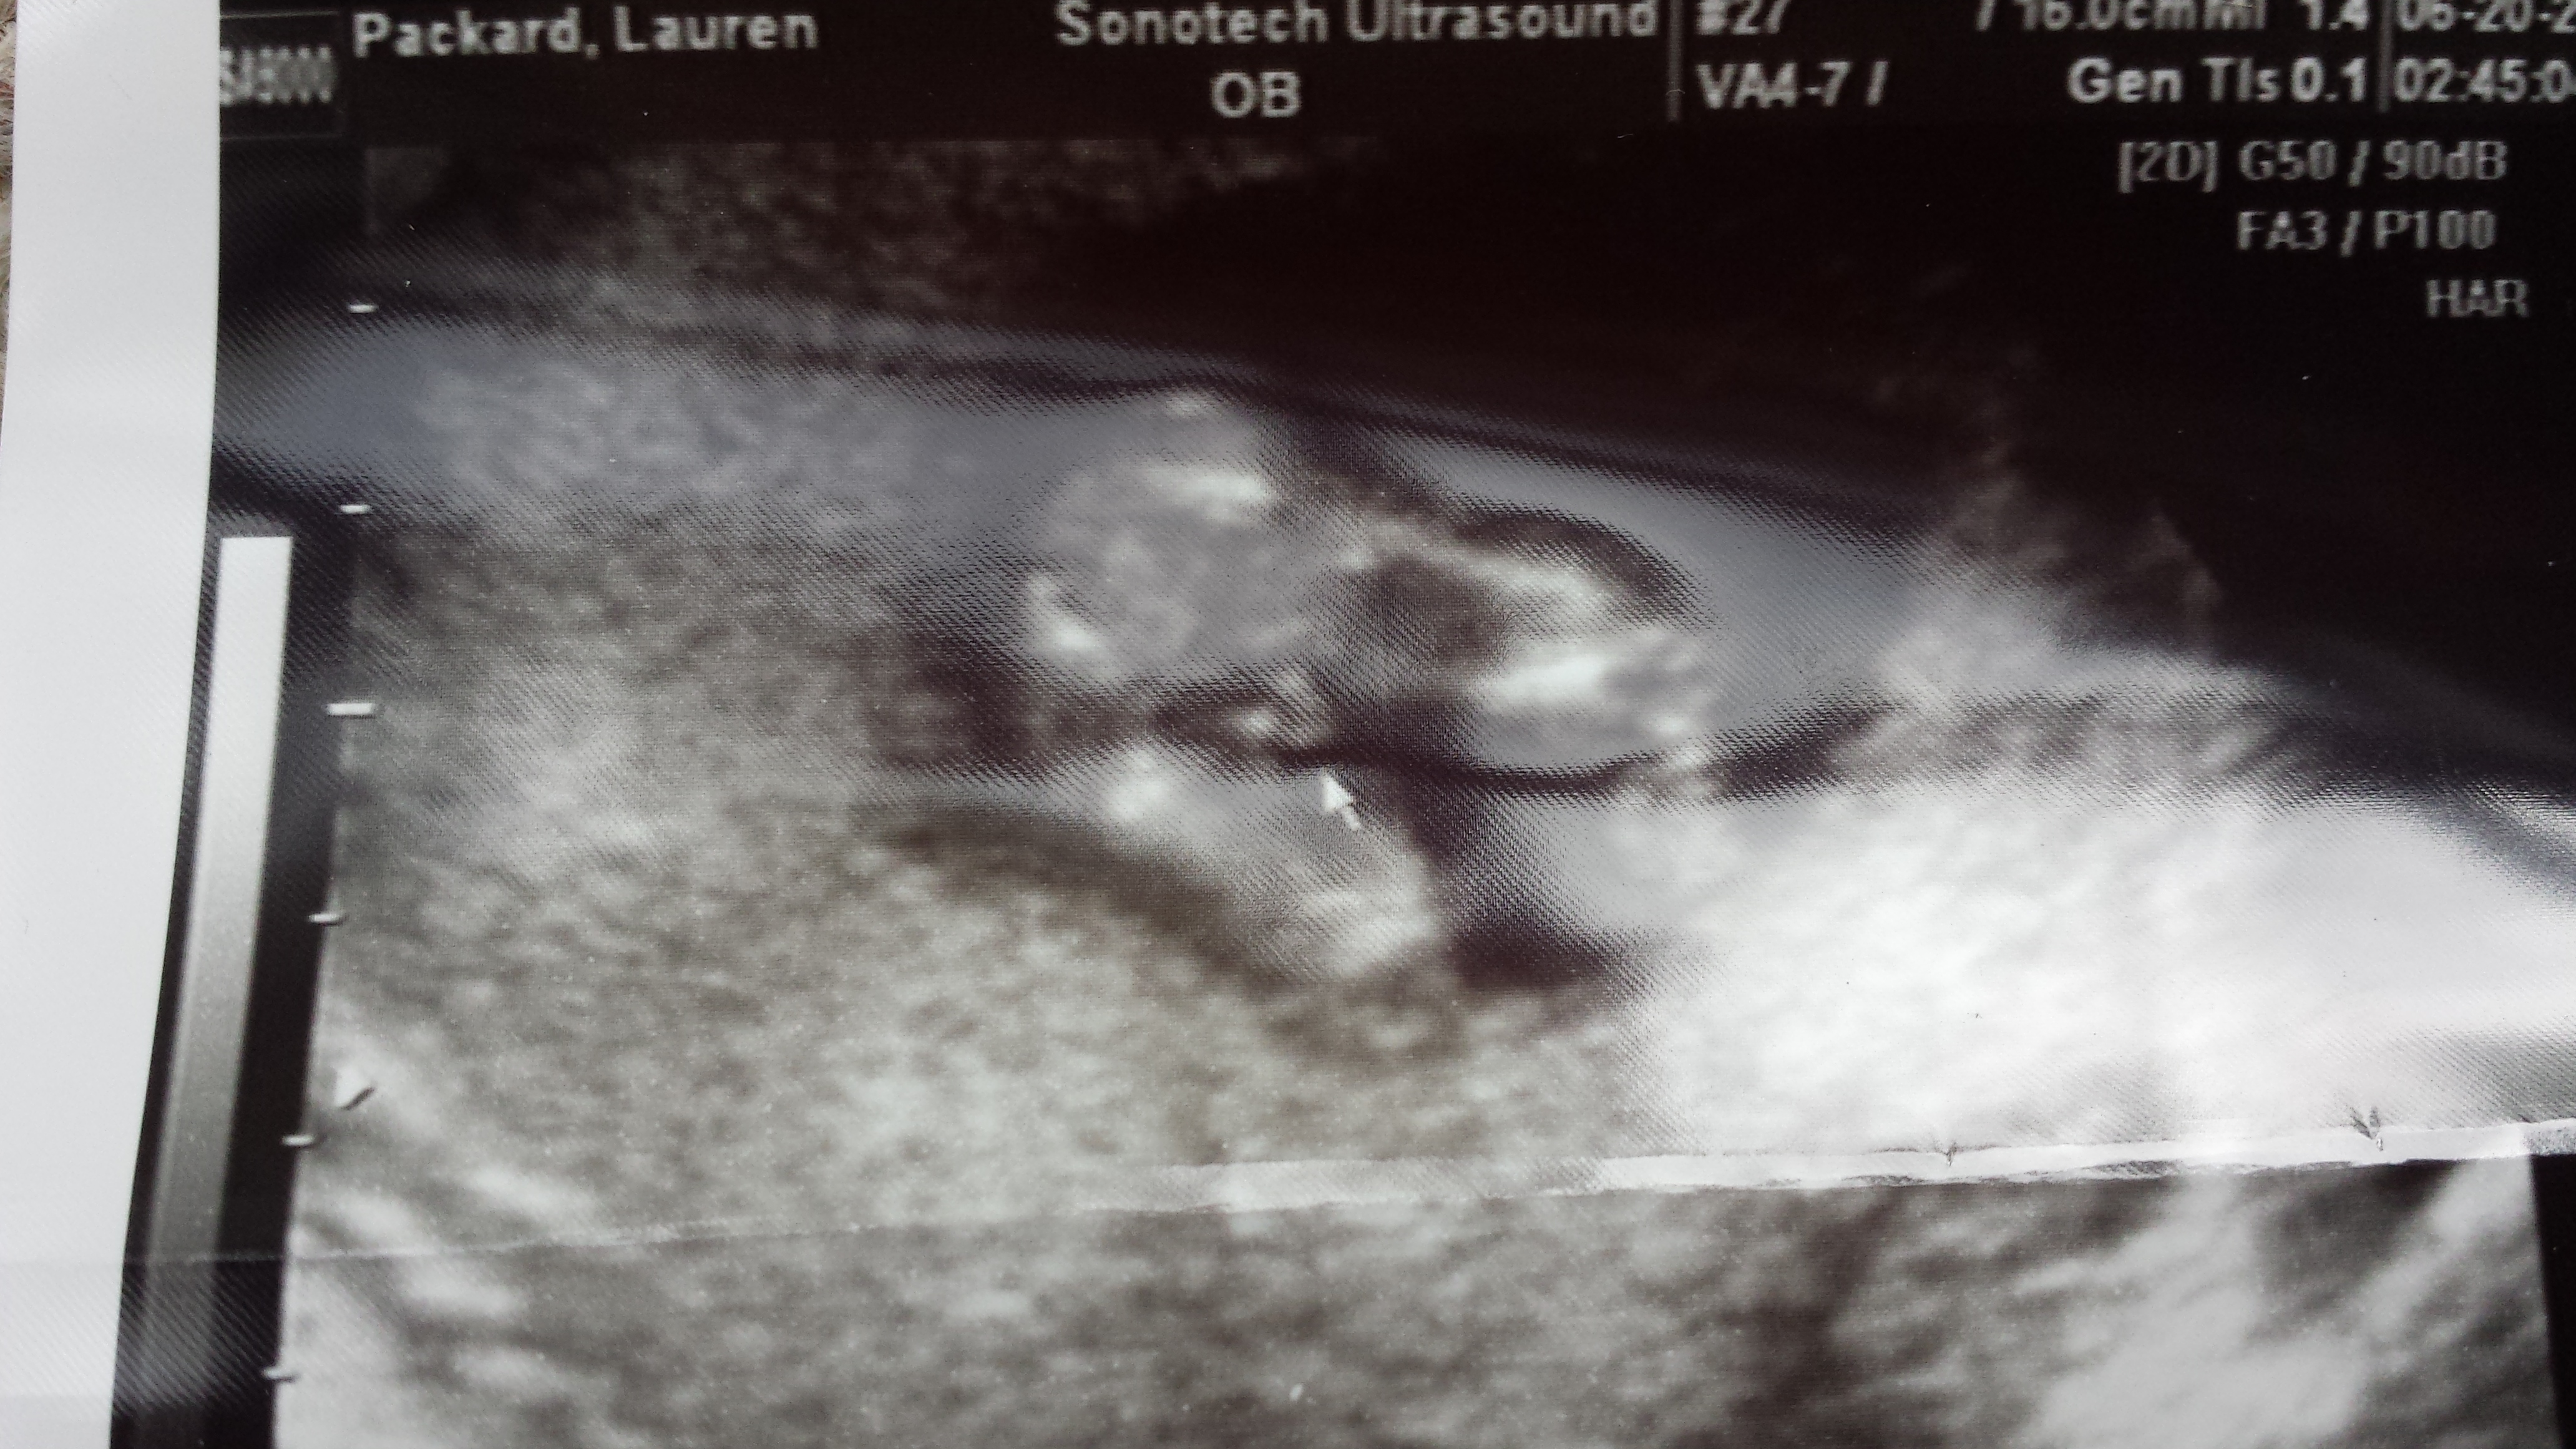

Confirmed boy....then confused:/

So I posted a couple of weeks ago my 12 almost 13 wk US photo which pretty clearly indicated boy. Then I got an elective US and tech confirmed boy. THEN I made the mistake of changing my midwife appt to a nurse appt because the tech found babies head measuring a week ahead and I wanted to discuss. Not only did she blow off my question about the dating/head size but she also indicated the tech could very well be wrong about the gender and treated me like a victim who had been taken advantage of. Totally lame! She definitely planted the seed of doubt when I was feeling very sure of everything- trying to move forward but super irritated. In any case, here are my "confirmed" potty shots. I still see pee pee and am disappointed in her behavior but was curious of your opinions and experiences dealing with not so great hospital staff. Back to he midwives next time!

Attachment 19519Attachment 19520